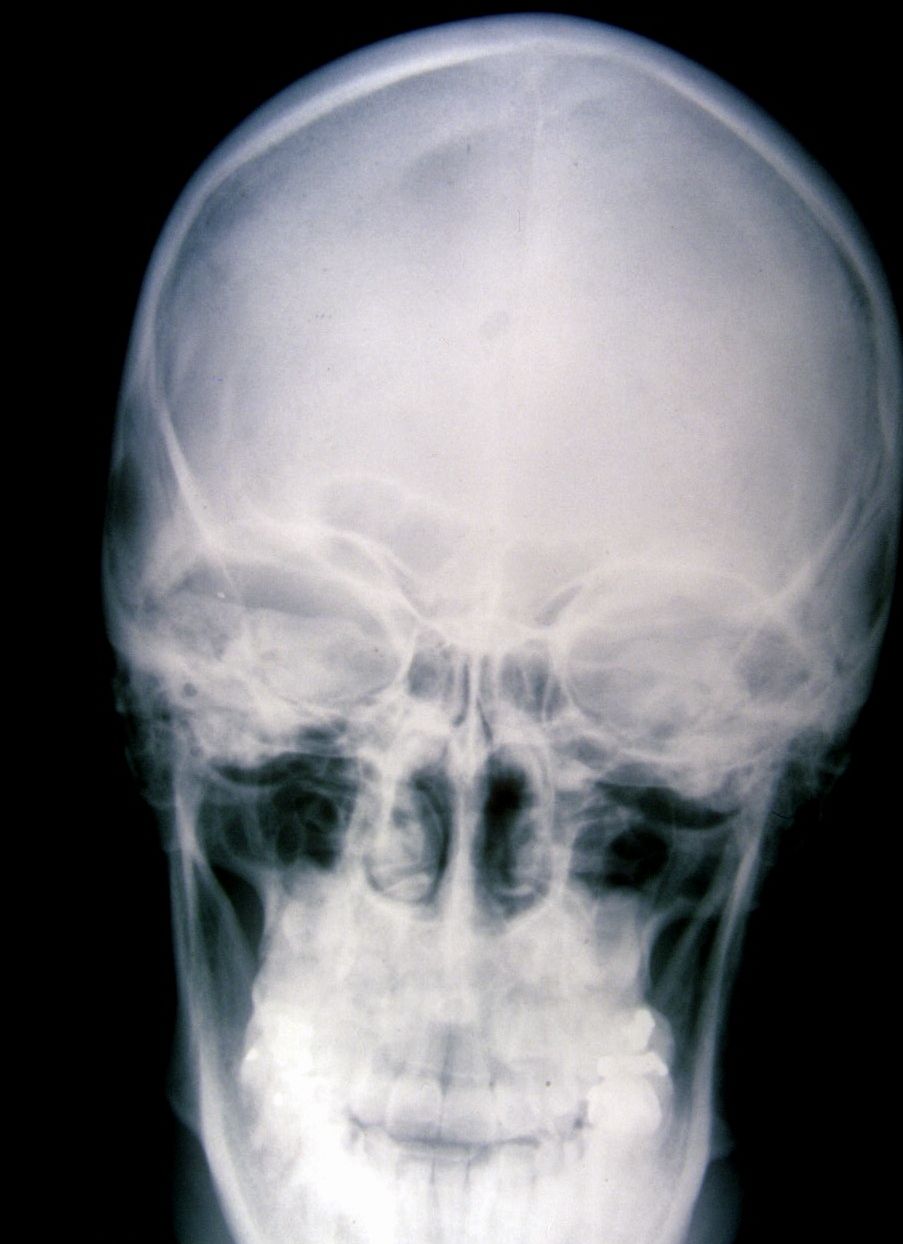

Seudoacondroplasia. [Pseudoachondroplasia]